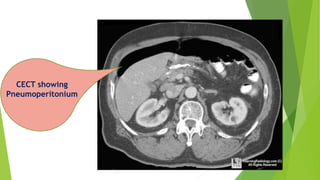

CECT abdomen

CECT showing

Pneumoperitonium